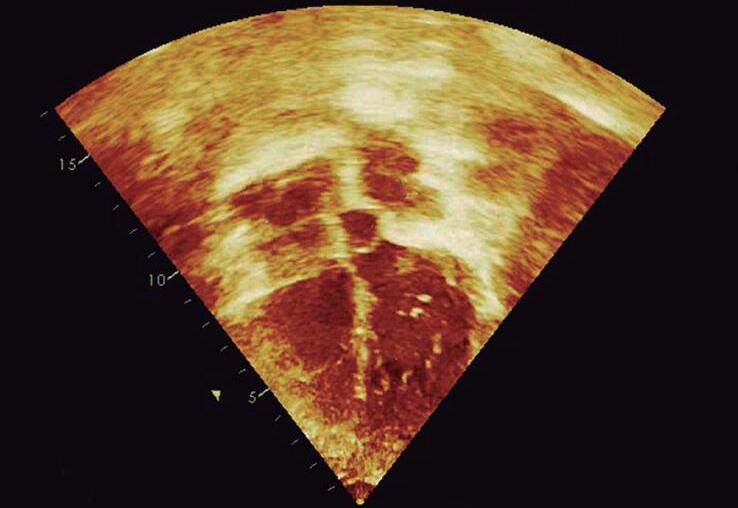

O paciente deve ser posicionado em decúbito dorsal com uma leve angulação do pescoço, com o auxílio de travesseiro colocado nas costas na altura dos ombros. O transdutor pode ser colocado nas regiões da fúrcula ou supraclavicular (direita e esquerda) (▶ Vídeo 1-31).

Inicialmente fazendo o eixo sagital com o index às “12 horas”, apontando posteriormente, obtemos a visão da aorta ascendente, ramos supra-aórticos e descendente (Fig. 1-13a e ▶ Vídeo 1-32). Em uma varredura, pode-se ver a aorta descendente e a sua localização no mediastino, ajudando assim a determinar a lateralidade do arco aórtico. A lateralidade aórtica está sendo abordada no Capítulo 11.

No eixo curto, com index do transdutor inicialmente em posição às “3 horas”, identificamos a veia inominada esquerda dirigindo-se para a veia cava superior direita e abaixo também demonstra a artéria pulmonar direita (▶ Vídeo 1-31). Em indivíduos menores, as veias pulmonares direitas e esquerdas são bem visualizadas e conectadas no átrio esquerdo (“imagem do caranguejo”) (Fig. 1-13b e ▶ Vídeo 1-33).

O mapeamento em cores é importante para definição do diâmetro, direção do fluxo e pesquisa de obstrução vascular. A veia inominada esquerda deve ser examinada por mapeamento de fluxo de cores para excluir a presença de uma veia superior esquerda.

Fig. 1-13. Ecocardiograma transtorácico demonstrando o plano supraesternal: (a) aorta torácica (ascendente, arco e descendente) e eixo curto (b) com artéria pulmonar direita, átrio esquerdo e as veias pulmonares. Ao: aorta; tbc: tronco braquiocefálico (1); ce: artéria carótida esquerda (2); asce: artéria subclávia esquerda (3); APD: artéria pulmonar direita; VCS: veia cava superior; AE: átrio esquerdo; VP; veia pulmonar.